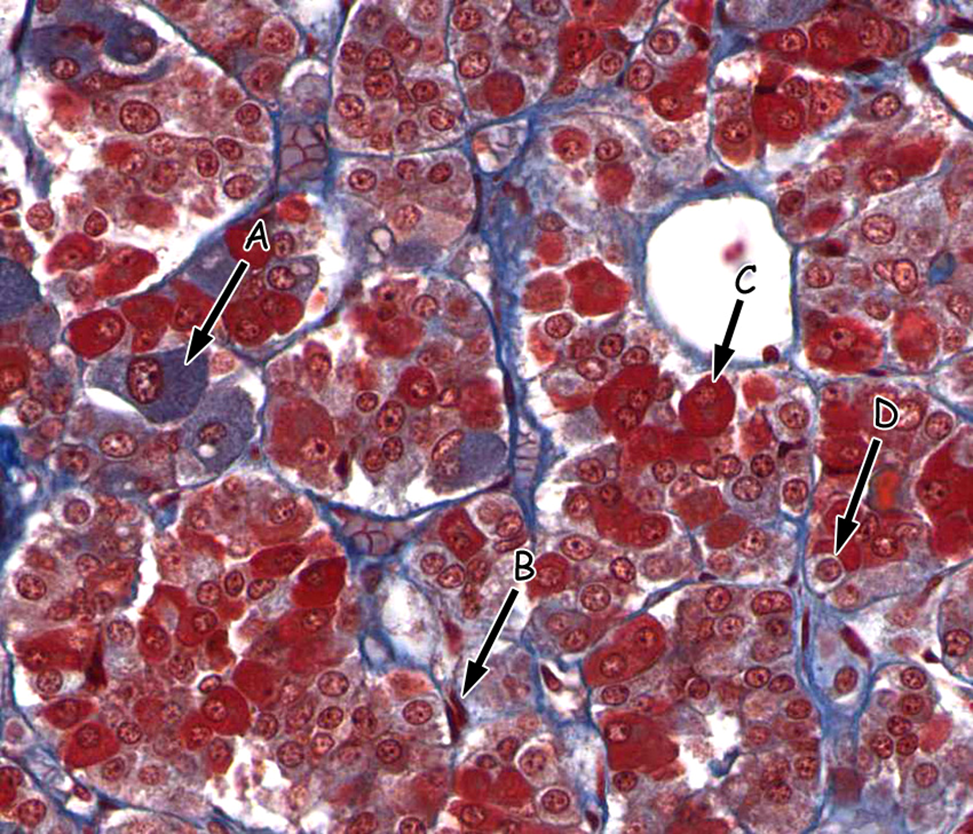

One possible cause of adrenal hyperplasia (hyperactivity) may be over-proliferation (e.g. a tumor) of which PITUITARY cell type indicated in this trichrome-stained section?

A. A

B. B

C. C

D. D

A

The zones of the adrenal gland are labeled in the attached image. Which zone synthesizes the largest amount of mineralocorticoids (such as aldosterone)?

A. A

B. B

C. C

D. D

E. E

B.B

Acromegaly leading to gigantism is caused by the excessive secretion of hormone from which of the following labeled cells?

A. A

B. B

C. C

D. D

C. C

The zones of the adrenal gland are labeled in the attached image. Overactivity of cells in which zone would cause virilization within women?

A. A

B.B

C. C

D.D

E.E

D. D